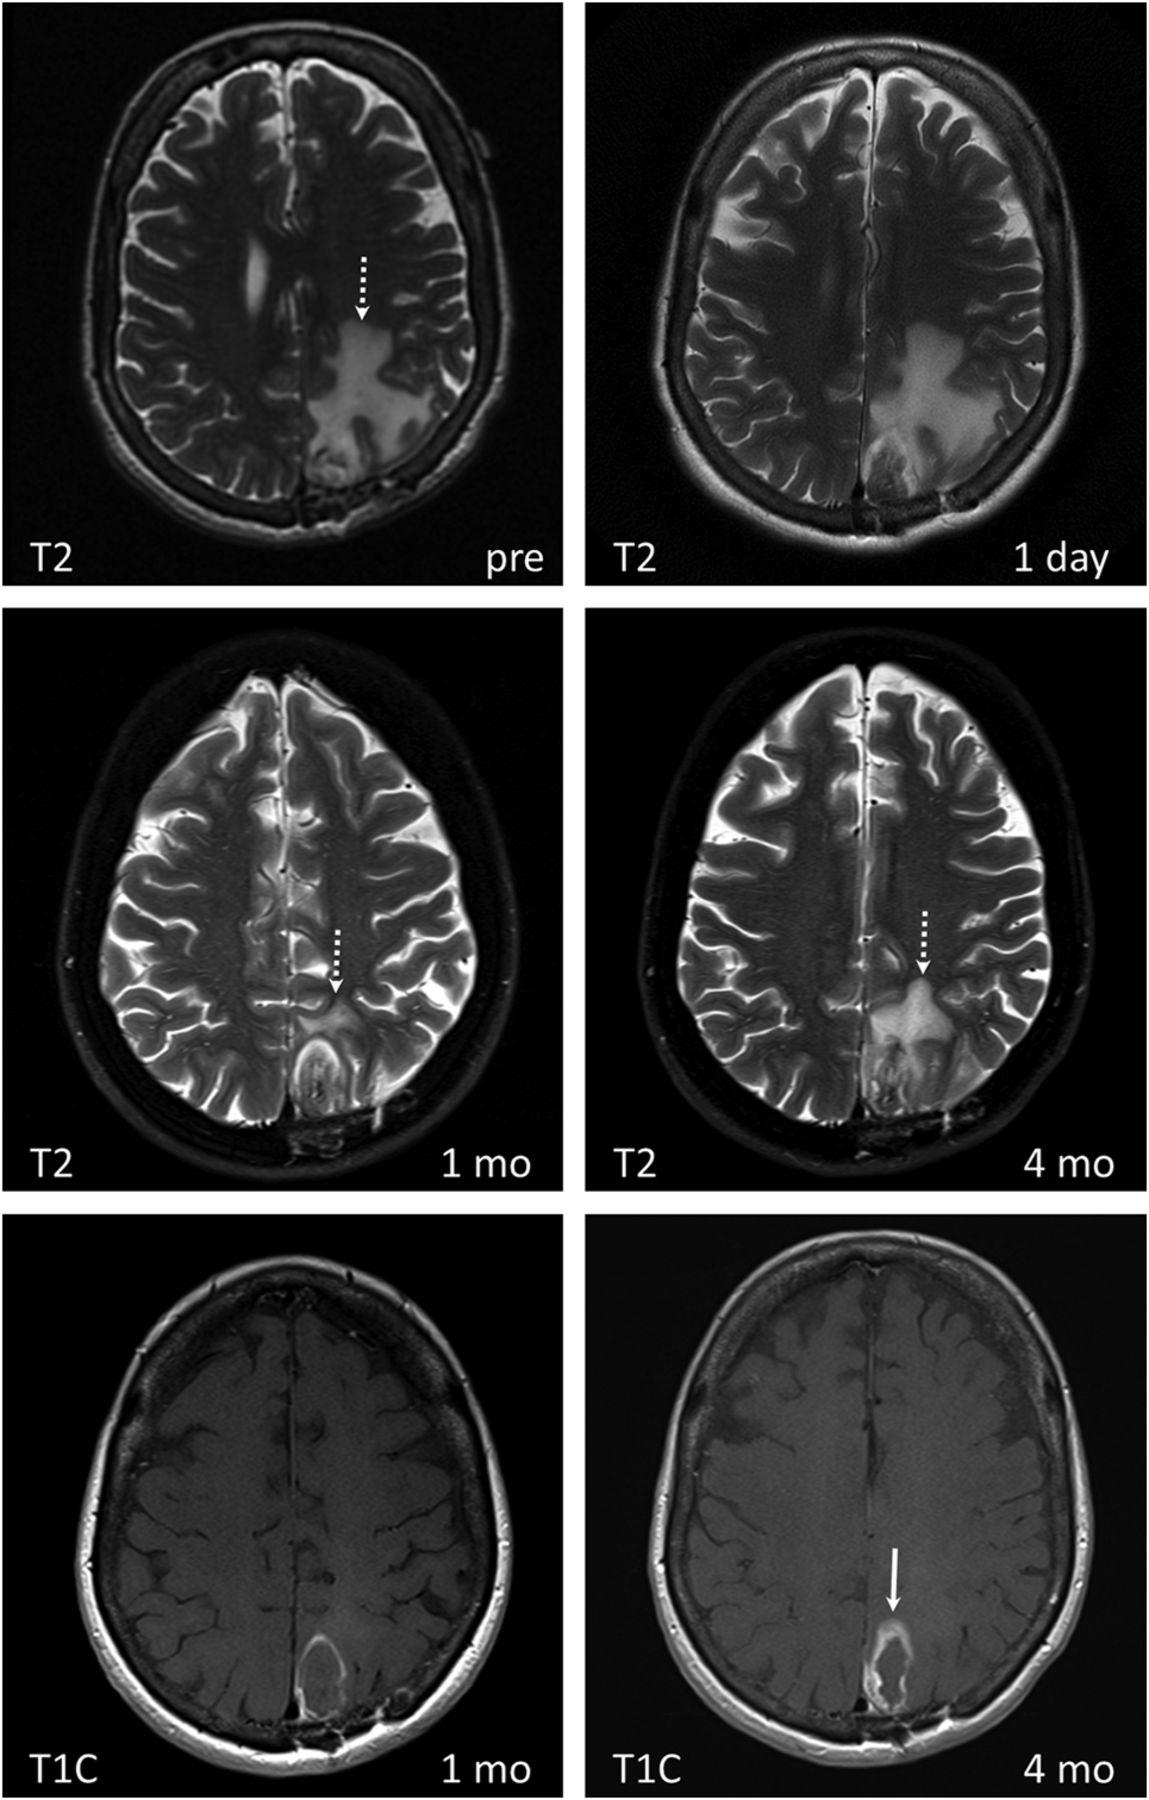

LITT of radiation necrosis with subsequent disease recurrence in a 68-year-old female patient with lung squamous cell carcinoma status post surgical excision and SRS of a metastatic brain lesion in the left parietal lobe, which subsequently resulted in radiation necrosis. Medically intractable radiation necrosis was treated with LITT. Pre-LITT imaging demonstrated an enhancing lesion in the left parietal lobe on T1 contrast-enhanced (not shown) with significant vasogenic edema on T2 images (dashed white arrow on T2 image labeled “pre”). Dynamic imaging pre-LITT (not shown) did not demonstrate a significant increase in CBF or CBV. The patient was not treated with bevacizumab, and RN was favored over recurrence. Note a significant decrease in vasogenic edema 1 month after treatment (dashed white arrow), coinciding with symptomatic improvement. T2 images obtained at 4-month follow-up demonstrate a significant increase in peritumoral vasogenic edema. There is significant thickening of the peripheral zone of enhancement (white arrow) on T1 contrast-enhanced images at 4 months compared with 1 month. Findings are concerning for tumor recurrence within a treated RN lesion, which was corroborated on PET CT (not shown).

The peripheral zone makes up the next concentric layer, which contains thrombosed vessels and distended cell bodies. This area undergoes delayed liquefaction necrosis and tends to enlarge during the first 1–40 days, followed by a continuous reduction in size thereafter.35 On MR imaging, this layer appears hypointense on T1 and hyperintense on T2 due to edema. The peripheral zone contains a thin peripherally enhancing rim on T1-weighted contrast-enhanced images, secondary to blood-brain barrier damage. The peripheral rim gradually changes in circumference and enhancement in accordance with changes in the entire peripheral zone. It generally decreases with time or may remain stable (Fig 3). Residual enhancement persists on long-term-follow-up, likely due to reactive inflammatory/granulation tissue. According to Rao et al,18 most lesions return to pretreatment size within 16 weeks. The outermost layer of the LITT lesion is the marginal zone, an area of reversible postsurgical perifocal edema, which appears hypointense on T1 and hyperintense on T2. This layer contains viable edematous tissue and demonstrates axonal swelling without thrombosis. It increases in size, reaching maximum dimensions at 1–3 days and gradually decreases in size during the course of 15 days to 2 months (Fig 4). In some cases, the marginal zone may demonstrate high T1 signal without corresponding susceptibility artifacts, likely due to the presence of myelin breakdown products. Patients are instructed to return for follow-up 1 month after ablation. Depending on imaging findings, clinical presentation, and type of disease, subsequent follow-up may be performed on a monthly basis or may be extended to longer intervals. There are no official follow-up recommendations.

Serial follow-up performed >40 days after the procedure should demonstrate a continuous decrease in the size of the ablated lesion and stable or decreased enhancement (Fig 3). Overall, the entire ablated lesion decreases to 50% of its original size within 93 days of treatment35 and continues to decrease in size for 6–15 months, becoming more homogeneous in appearance. Peripheral enhancement that persists or gradually decreases in size is a sign of the normal evolution of the ablated lesion. Any interval increase in lesion size, heterogeneity, peripheral nodular enhancement, restricted diffusion, CBF/CBV, and surrounding edema in a lesion treated >40–60 days prior should raise suspicion for recurrence (Fig 5).36,37 Recurrence usually occurs within the peripheral rim of enhancement and presents as new or enlarging peripheral enhancing nodularity (Figs 5) or simply as thickening of the rim of enhancement (Fig 6). Comparison with prior images is vital in monitoring tumor recurrence because normally evolving lesions can demonstrate asymmetric enhancement similar to that of recurring lesions. Therefore, irregularly enhancing lesions require close-interval follow-up. Any increase in size, enhancement, or surrounding edema should be further assessed with adjunctive techniques such as MR spectroscopy, perfusion imaging, or PET.